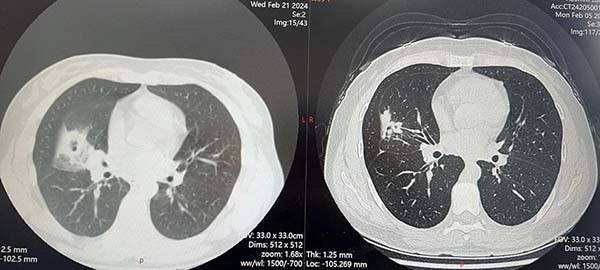

平静幸福的生活被两年前的体检打破,当地45岁以上人群开展健康体检,刘女士被发现肺内结节,当地医院胸部CT提示:多发结节伴空洞,考虑结核可能。刘女士虽是家庭妇女,但喜欢看一些医学科普,了解肺结核有慢性咳嗽、咳痰、消瘦、乏力、盗汗等症状,自己没有任何症状,怎么自己就得肺结核了呢?

一番判断后,他给出了初步意见:“你的各项检查没有发现结核菌,结核病的诊断依据并不充分。而且已经接受了18个月的规范抗结核治疗,但肺部病灶没有得到控制,基本可以排除肺结核;另外,你的抗环瓜氨酸肽抗体阳性,这项检查诊断类风湿性关节炎的特异性超过 90%,类风湿关节炎相关的肺结节可能性大。”段鸿飞说,“你这个不像结核,治了这么久没效果,早就应该考虑其他的问题了。我初步怀疑是非感染性疾病的肺部病变,也就是这些疾病不是外来细菌或者病毒带来的,很可能是您自身带来的。去看看血管炎或者风湿免疫吧。”